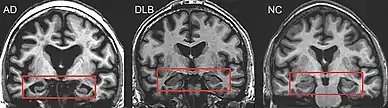

Direct laboratory-measurable biomarkers for DLB diagnosis are not known, but several indirect methods can lend further evidence for diagnosis.[25] The indicative diagnostic biomarkers are: reduced dopamine transporter uptake in the basal ganglia shown on PET or SPECT imaging; low uptake of 123iodine-metaiodobenzylguanidine (123I-MIBG) shown on myocardial scintigraphy; and loss of atonia during REM sleep evidenced on polysomnography. Supportive diagnostic biomarkers (from PET, SPECT, CT, or MRI brain imaging studies or EEG monitoring[124]) are: lack of damage to medial temporal lobe (damage is more likely in AD[116]); reduced occipital activity; and prominent slow-wave activity on EEG.[25]

Lewy pathology affects the peripheral autonomic nervous system; autonomic dysfunction is observed less often in AD, frontotemporal, or vascular dementias, so its presence can help differentiate them.[141] MRI scans almost always show abnormalities in the brains of people with vascular dementia, which can begin suddenly.[142]

Alzheimer's disease

DLB is distinguishable from AD even in the prodromal phase.[23] Short-term memory impairment is seen early in AD and is a prominent feature, while fluctuating attention is uncommon; impairment in DLB is more often seen first as fluctuating cognition.[143] In contrast to AD—in which the hippocampus is among the first brain structures affected, and episodic memory loss related to encoding of memories is typically the earliest symptom—memory impairment occurs later in DLB.[39][144] People with amnestic mild cognitive impairment (in which memory loss is the main symptom) may progress to AD, whereas those with non-amnestic mild cognitive impairment (which has more prominent impairments in language, visuospatial, and executive domains) are more likely to progress towards DLB.[145] Memory loss in DLB has a different progression from AD because frontal structures are involved earlier, with later involvement of temporoparietal brain structures.[144] Verbal memory is not as severely affected as in AD.[146]

PET or SPECT imaging can be used to detect reduced dopamine transporter uptake and distinguish AD from DLB.[57][149] Severe atrophy of the hippocampus is more typical of AD than DLB.[150] Before dementia develops (during the mild cognitive impairment phase), MRI scans show normal hippocampal volume. After dementia develops, MRI shows more atrophy among individuals with AD, and a slower reduction in volume over time among people with DLB than those with AD.[33] Compared to people with AD, FDG-PET brain scans in people with DLB often show a cingulate island sign.[33]